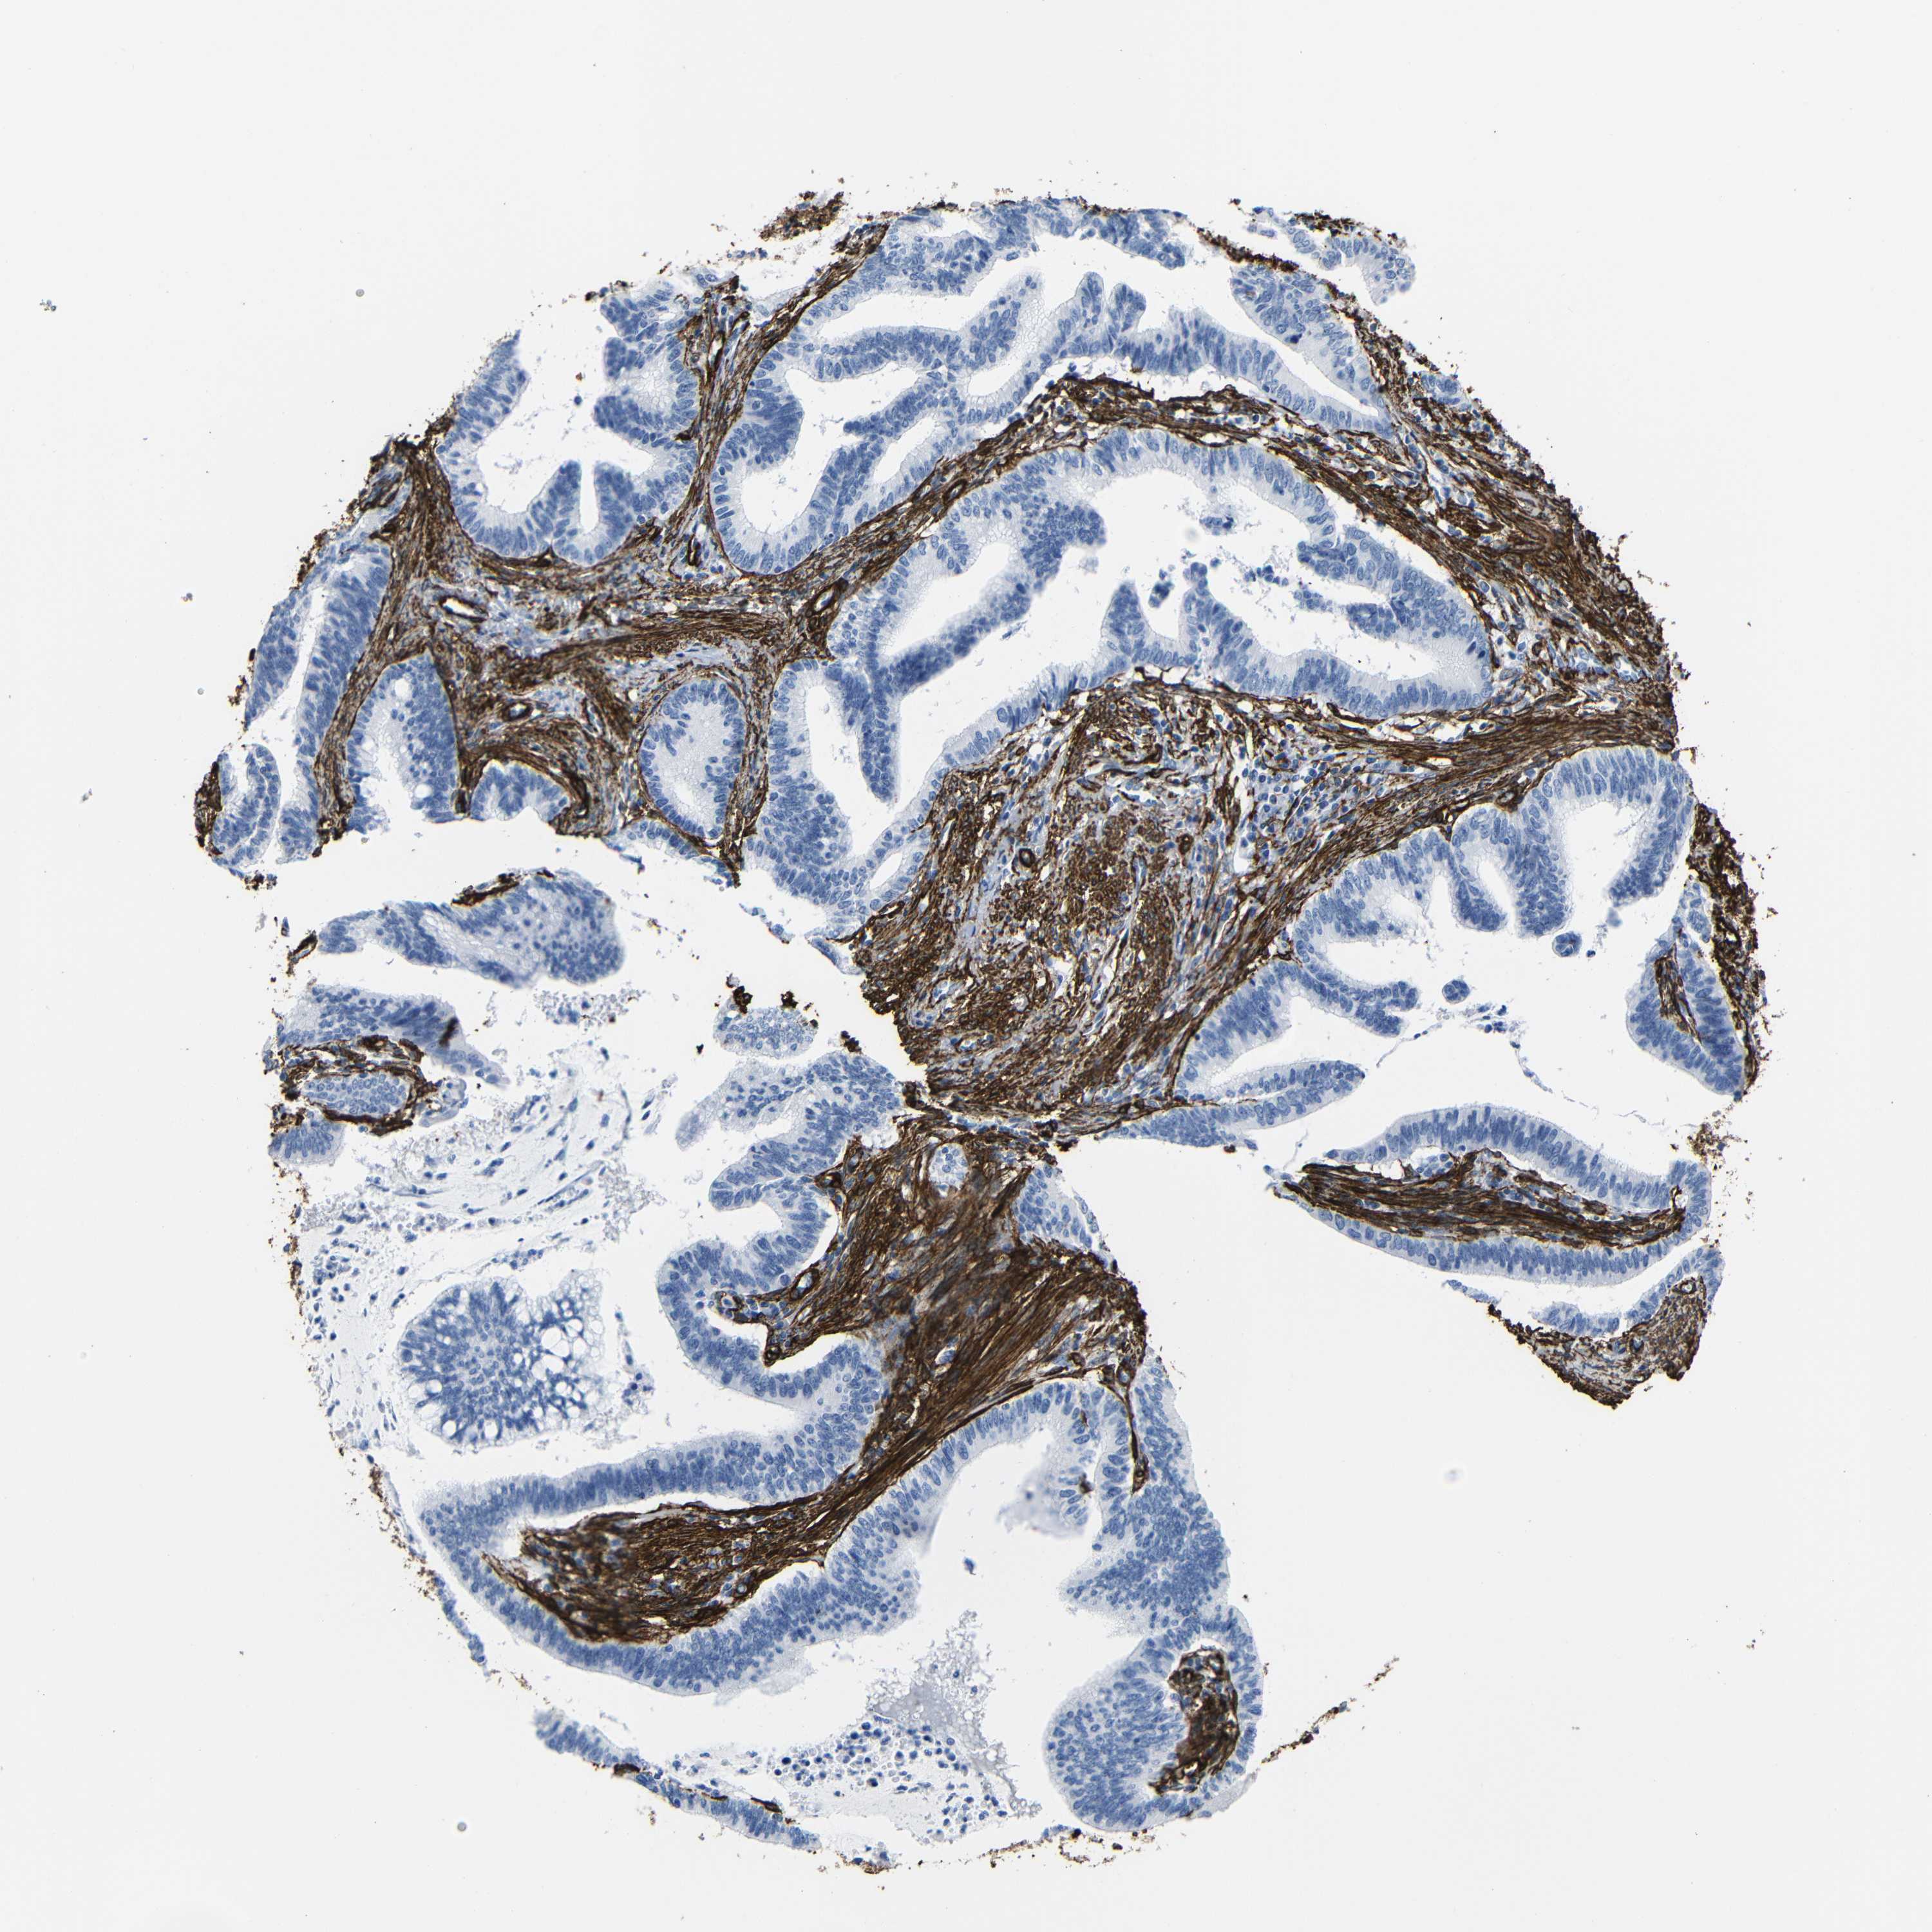

CERVICAL CANCER - Protein expressioni

A mouse-over function shows sample information and annotation data. Click on an image to view it in a full screen mode. Samples can be filtered based on level of antibody staining by selecting one or several of the following categories: high, medium, low and not detected. The assay and annotation is described here.

Note that samples used for immunohistochemistry by the Human Protein Atlas do not correspond to samples in the TCGA dataset.

Antibody stainingi

Antibody staining in the annotated cell types in the current human tissue is reported as not detected, low, medium, or high, based on conventional immunohistochemistry profiling in selected tissues. This score is based on the combination of the staining intensity and fraction of stained cells.

Each image is clickable and will lead to virtual microscopy that enables deeper exploration of all samples and also displays staining intensity scores, fraction scores and subcellular localization as well as patient and tissue information for each sample.

HPA041264

HPA041271

CAB000002

CAB003761

CAB013531

Staining

High

Medium

Low

Not detected

Intensity

Strong

Moderate

Weak

Negative

Quantity

>75%

75%-25%

<25%

None

Location

Nuclear

Cytoplasmic/membranous

Cytoplasmic/membranous,nuclear

Squamous cell carcinoma, NOS

Adenocarcinoma, NOS